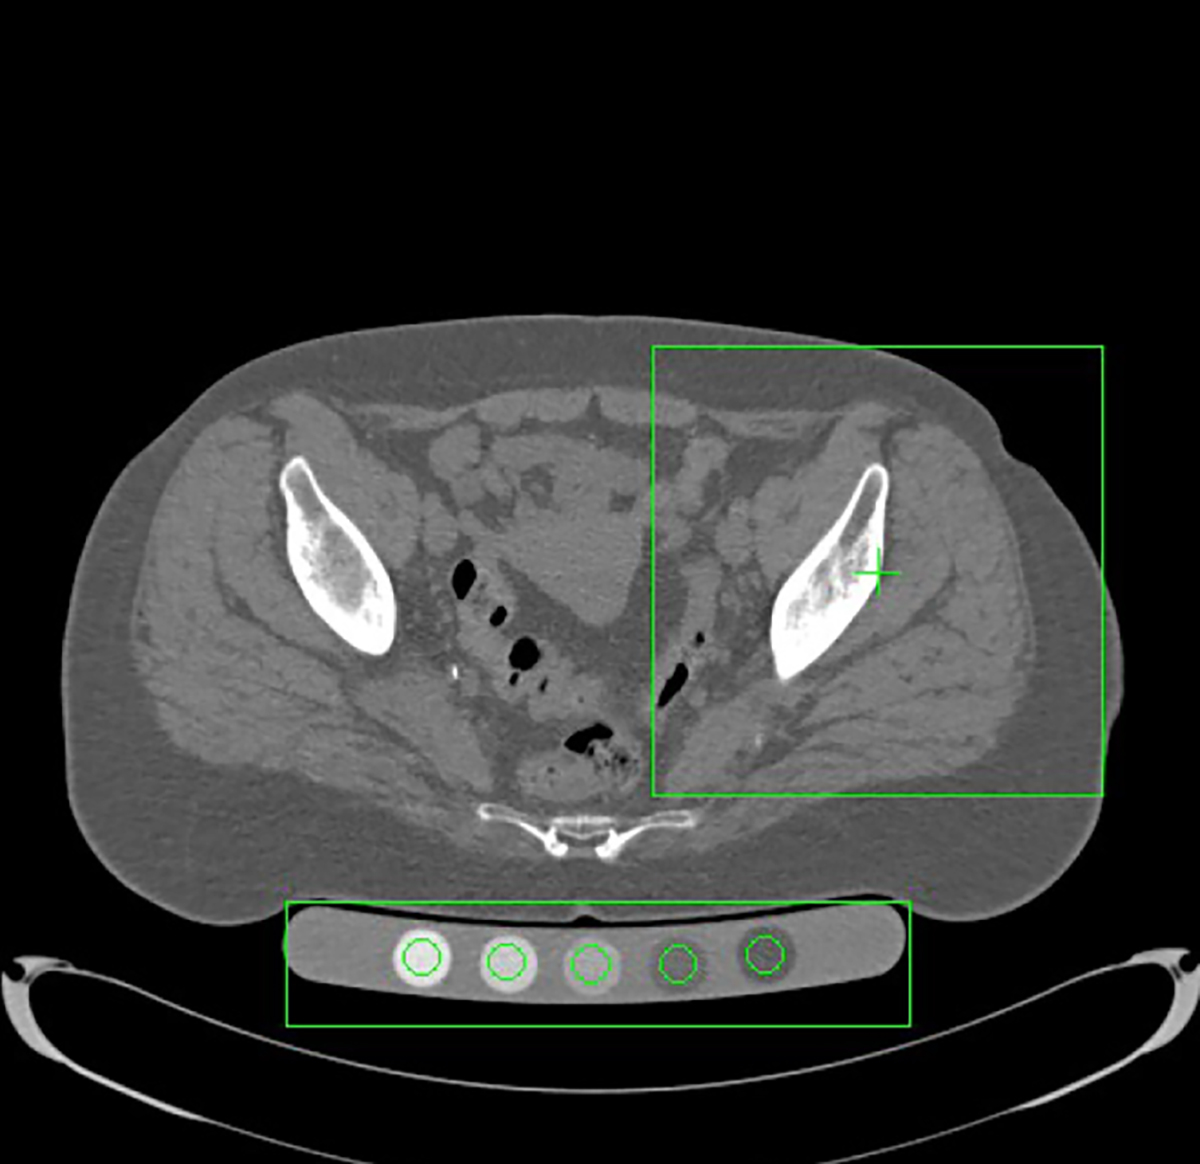

Automatic selection of regions of interest (ROIs) for QCT analysis. Axial CT slice processed with the CTXA Hip module (QCT Pro, Mindways). The green boxes indicate the automated placement of the hip ROI and the calibration phantom, which are used to extract bone mineral density values for osteoporosis assessment.